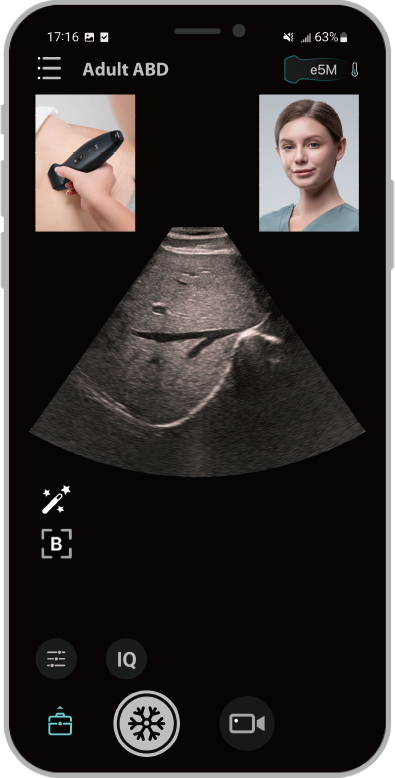

iScanHelper: um tutorial integrado

Fornece orienta??o fĂĄcil de seguir sobre o exame de ultrassom com ilustra??es anat?micas, imagens padr?o, imagens de referĂȘncia e dicas prĂĄticas para um exame eficaz